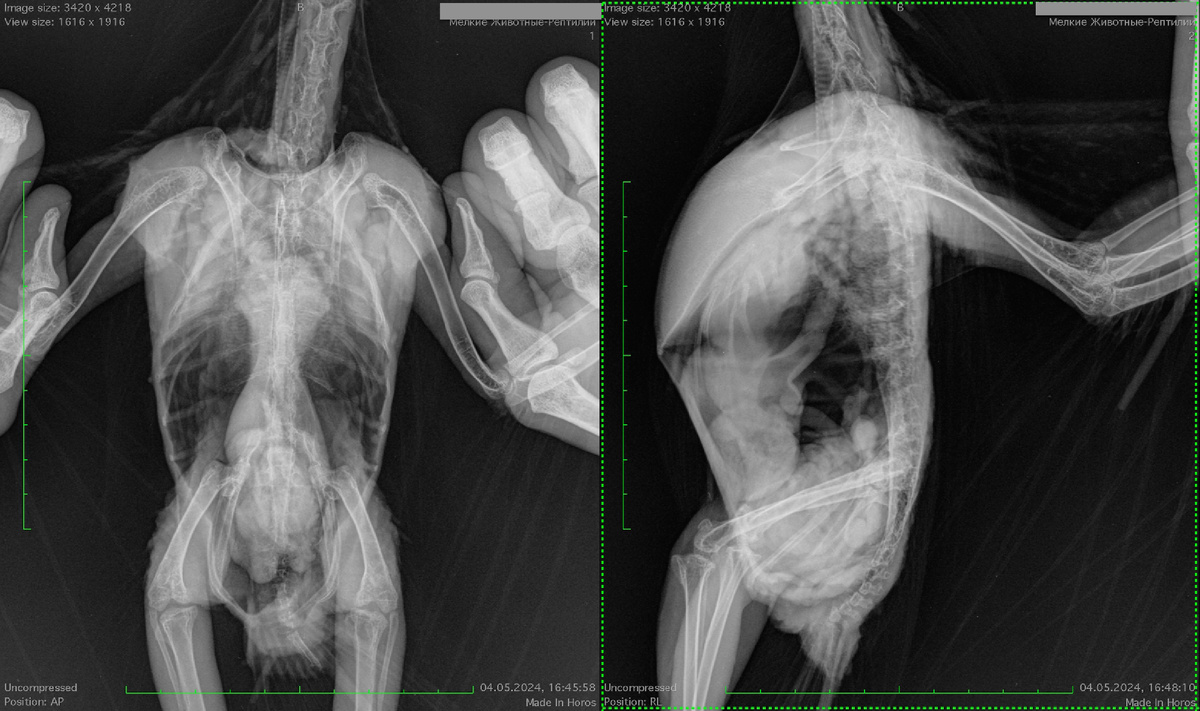

Примерно такая картина видна на первом рентгене моего пациента какаду, которого я лечу от комплекса инфекций, в том числе от борнавироза.

на рентгене какаду хорошо виден огромный железистый желудок, который занимает почти всю целомическую полость попугая. Это основной признак борнавироза на рентгене.

То есть это рахитичная птица, почти сразу же у нее был обнаружен микобактериз вызванный M.genavense, далее было очень много анализов, лечение от кучи всякой вторичной микрофлоры, в том числе заражение от человека MRSA, и т.д., но борнавироз не удавалось подтвердить, лечение от борнавироза было назначего по изменениям увиденным на рентгене, и через 4 года лечения результат можно увидеть на втором рентгене.